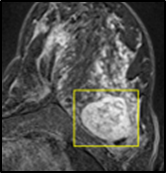

The proposed method starts with selecting a particular slice of breast MRI volume, performed by an expert radiologist, such that it contains at least one lesion. The slice image is normally the subtraction of pre-contrast and post-contrast images. The ground truth segmentation provided by expert radiologists and ROI is drawn around the lesion manually. As a pre-processing step, We applied contrast limited adaptive histogram equalization (CLAHE) [12] on that particular slice globally to improve lesion contrast. Then we computed the morphological gradient of the image, which is the point-wise difference between a unitary dilation and erosion.

In MR images, tumor regions are normally brighter and have more uniform intensity than the neighbouring healthy tissue. Based on this fact, we determined the internal and external markers by sorting out the pixel values in ROIs in descending order and chose pixels with maximum intensity values as markers. After selecting the markers the normal watershed transformation is applied on the ROIs image which is shown in Fig 1 Finally, a binary mask is generated based on watershed output regions. However, we identified the optimal number of markers based on segmentation accuracy evaluated using Dice and Jaccard.

where refers to the ROIs segmented by our algorithm and is tumor area as determined by manual segmentation. Table 1 summarizes the segmentation accuracy achieved using the proposed method for all 106 cases. The average dice coefficient was found to be 0.780.17 and average Jaccard index was 0.670.21. Fig 3 demonstrate four sample segmentation outputs which are overlaid on manual segmentations provided by two radiologists. It can be seen, that the proposed method could accurately segment the lesions with some marginal errors for medium to large tumors. However, for cases comprising disjoint lesions, the method failed to segment all small lesions and in some cases incorrectly labeled healthy tissue as lesions. This is because in some cases there is a high degree of overlap in the intensity distributions of healthy breast tissue and lesions, and the ROI drawn by the radiologist is very large in the case of disjoint lesions, in order to cover the entire area over which multiple lesions are distributed.